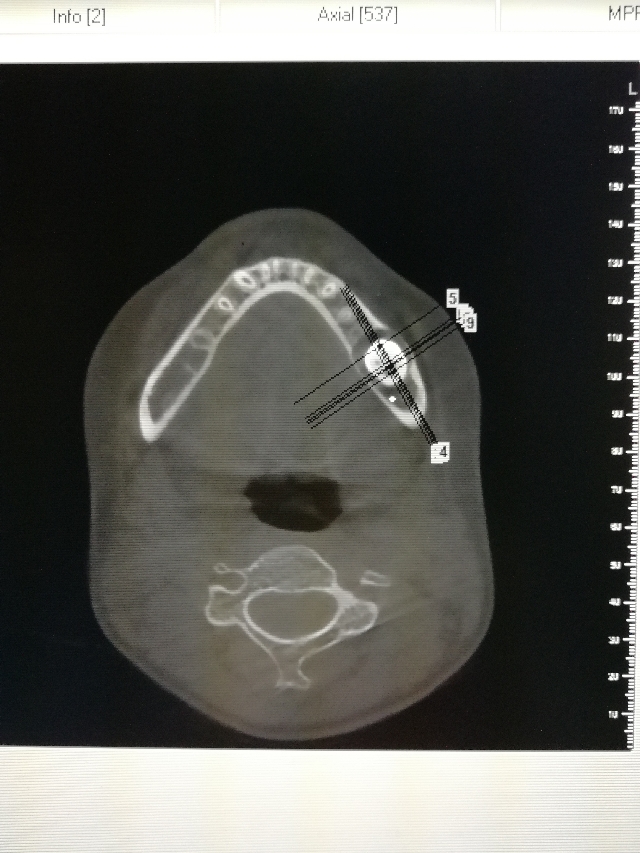

口腔检查:左下六龄牙(36)未萌出,其它3个六龄牙均正常萌出建合。

放射检查见片: 处理:局麻下拔除36